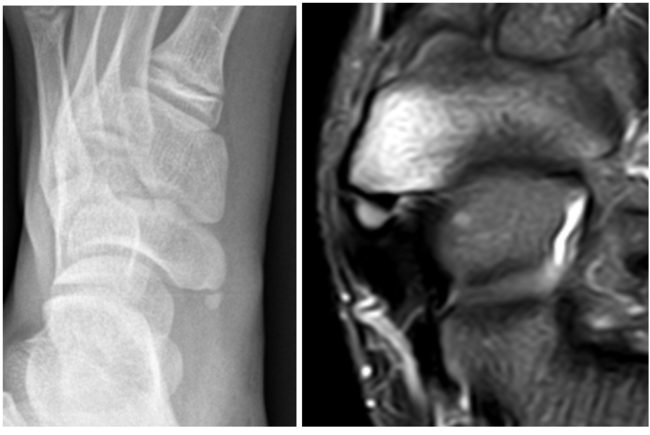

MRI 검사 상에서 보이는 것과 같이 골부종이 발생하게 되면 비수술적인 치료에도 불구하고 통증이 오랜 기간 지속되며, 이에 부착하는 후경골건에도 영향을 주게 된다. 또, 평발과의 연관성도 있는 것으로 알려져 있어 통증은 물론 스포츠 활동에 있어서 순발력, 스피드 저하와 같은 기능적인 면에서도 악영향을 미치게 된다.

[사진] 부주상골 증후군이 발발한 부위. 아래는 X-레이와 MRI 사진.